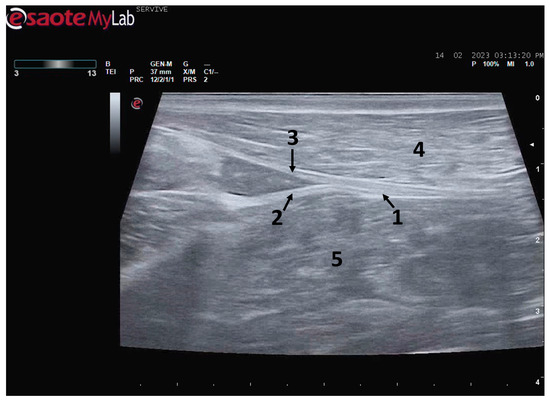

Figure 5.

Ultrasound image of the left sciatic nerve and its ramifications in a sheep: (1) sciatic nerve, identified by an arrow; (2) tibial nerve, identified by an arrow; (3) common peroneal nerve, identified by an arrow; (4) biceps femoris muscle; (5) adductor muscles.

At the level of the stifle, and with great interindividual variation, the two branches of the sciatic nerve, the common peroneal nerve, and the tibial nerve, are easily observable and distinguishable, diverging from the main nerve (Figure 5). Both the sciatic nerve and its branches appear as hypoechogenic neuronal tubular structures (nerve fascicles and the perineurium) surrounded by a hyperechogenic envelope corresponding to the connective tissue nerve wrappings (epineurium) (Figure 3, Figure 4 and Figure 5). The most lateral nerve, appearing dorsally on the ultrasound image, corresponds to the common peroneal nerve and imagiologically has a slightly smaller diameter than the tibial nerve, which is more medial and appears ventrally on the ultrasound image. Accompanying both nerves distally, there is a tendency for a slight decrease in their diameter before the final ramifications, but the intended site for inducing injury to the common peroneal nerve is proximal to the point where the decrease in diameter occurs.

After the branching of the sciatic nerve into its main branches, the common peroneal nerve arises laterally regarding the tibial nerve (dorsally in the ultrasound image), projecting in its course towards the extensor muscles of the fingers and flexors of the tarsus and presenting a systematically smaller diameter than that of the tibial nerve, as described in the literature for other species [16,28]. The latter arises medially (ventrally in the ultrasound image), projecting towards the flexor muscles of the fingers and extensor muscles of the tarsus, with a larger diameter. The diameter of the common peroneal nerve is identical to that previously identified in this species through stereology techniques [9]. It is expected that the diameter of the three nerves may vary according to the size of the animals, but as all the sheep used in this work had identical body dimensions, no significant variations were observed. The ultrasound aspect of the common peroneal and tibial nerves is identical to that of the sciatic nerve, and the difficulty in observing these nerves arises distally, where their diameter can be significantly reduced before their final ramifications. Despite this, this fact should not be a limitation in experimental work since the intended site for inducing lesions in the common peroneal nerve will be shortly after the site of emergence under the biceps femoris muscle, where the nerve becomes superficial but still has significant dimensions that will allow easy identification, isolation, induction of lesions and application of therapeutic options [9].